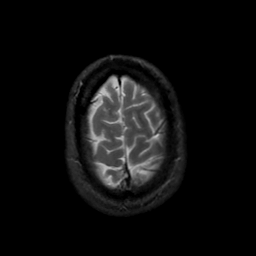

MR Study #22, December 1, 1991 -- Slice #44

[Home][Help][Clinical][Tour 1][Tour 2] Slice 44